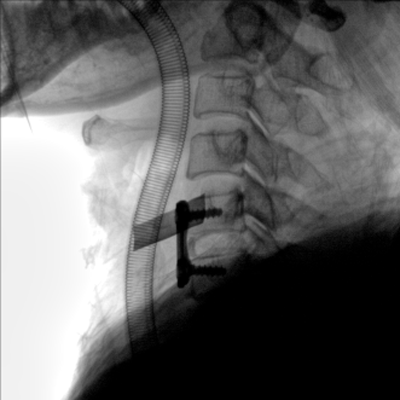

臨床適用科室:骨科、普通外科、矯形外科、創(chuàng)傷外科、泌尿外科、脊柱外科、疼痛外科、消化科、婦科等科室。

大尺寸動(dòng)態(tài)平板探測(cè)器,高DQE、低噪聲、圖像清晰。采用多分辨率圖像增強(qiáng)處理技術(shù),不同部位不同圖像處理算法,滿足客戶多樣化的需求。

采用智能變頻脈沖透視技術(shù),優(yōu)化圖像質(zhì)量的同時(shí)降低輻射劑量,呵護(hù)醫(yī)患健康